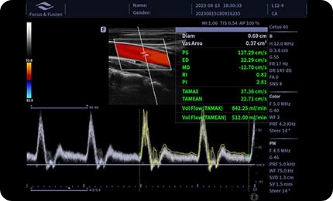

Auto Volume Flow

Mierzenie powierzchni naczynia krwionośnego, prędkość przepływu krwi może być automatycznie mierzona przez spektrum, a wyniki objętości przepływu krwi zostaną wyświetlone.

Auto IMT

Mierzenie powierzchni naczynia krwionośnego, prędkość przepływu krwi może być automatycznie mierzona przez spektrum, a wyniki objętości przepływu krwi zostaną wyświetlone.

Obrazy kliniczne